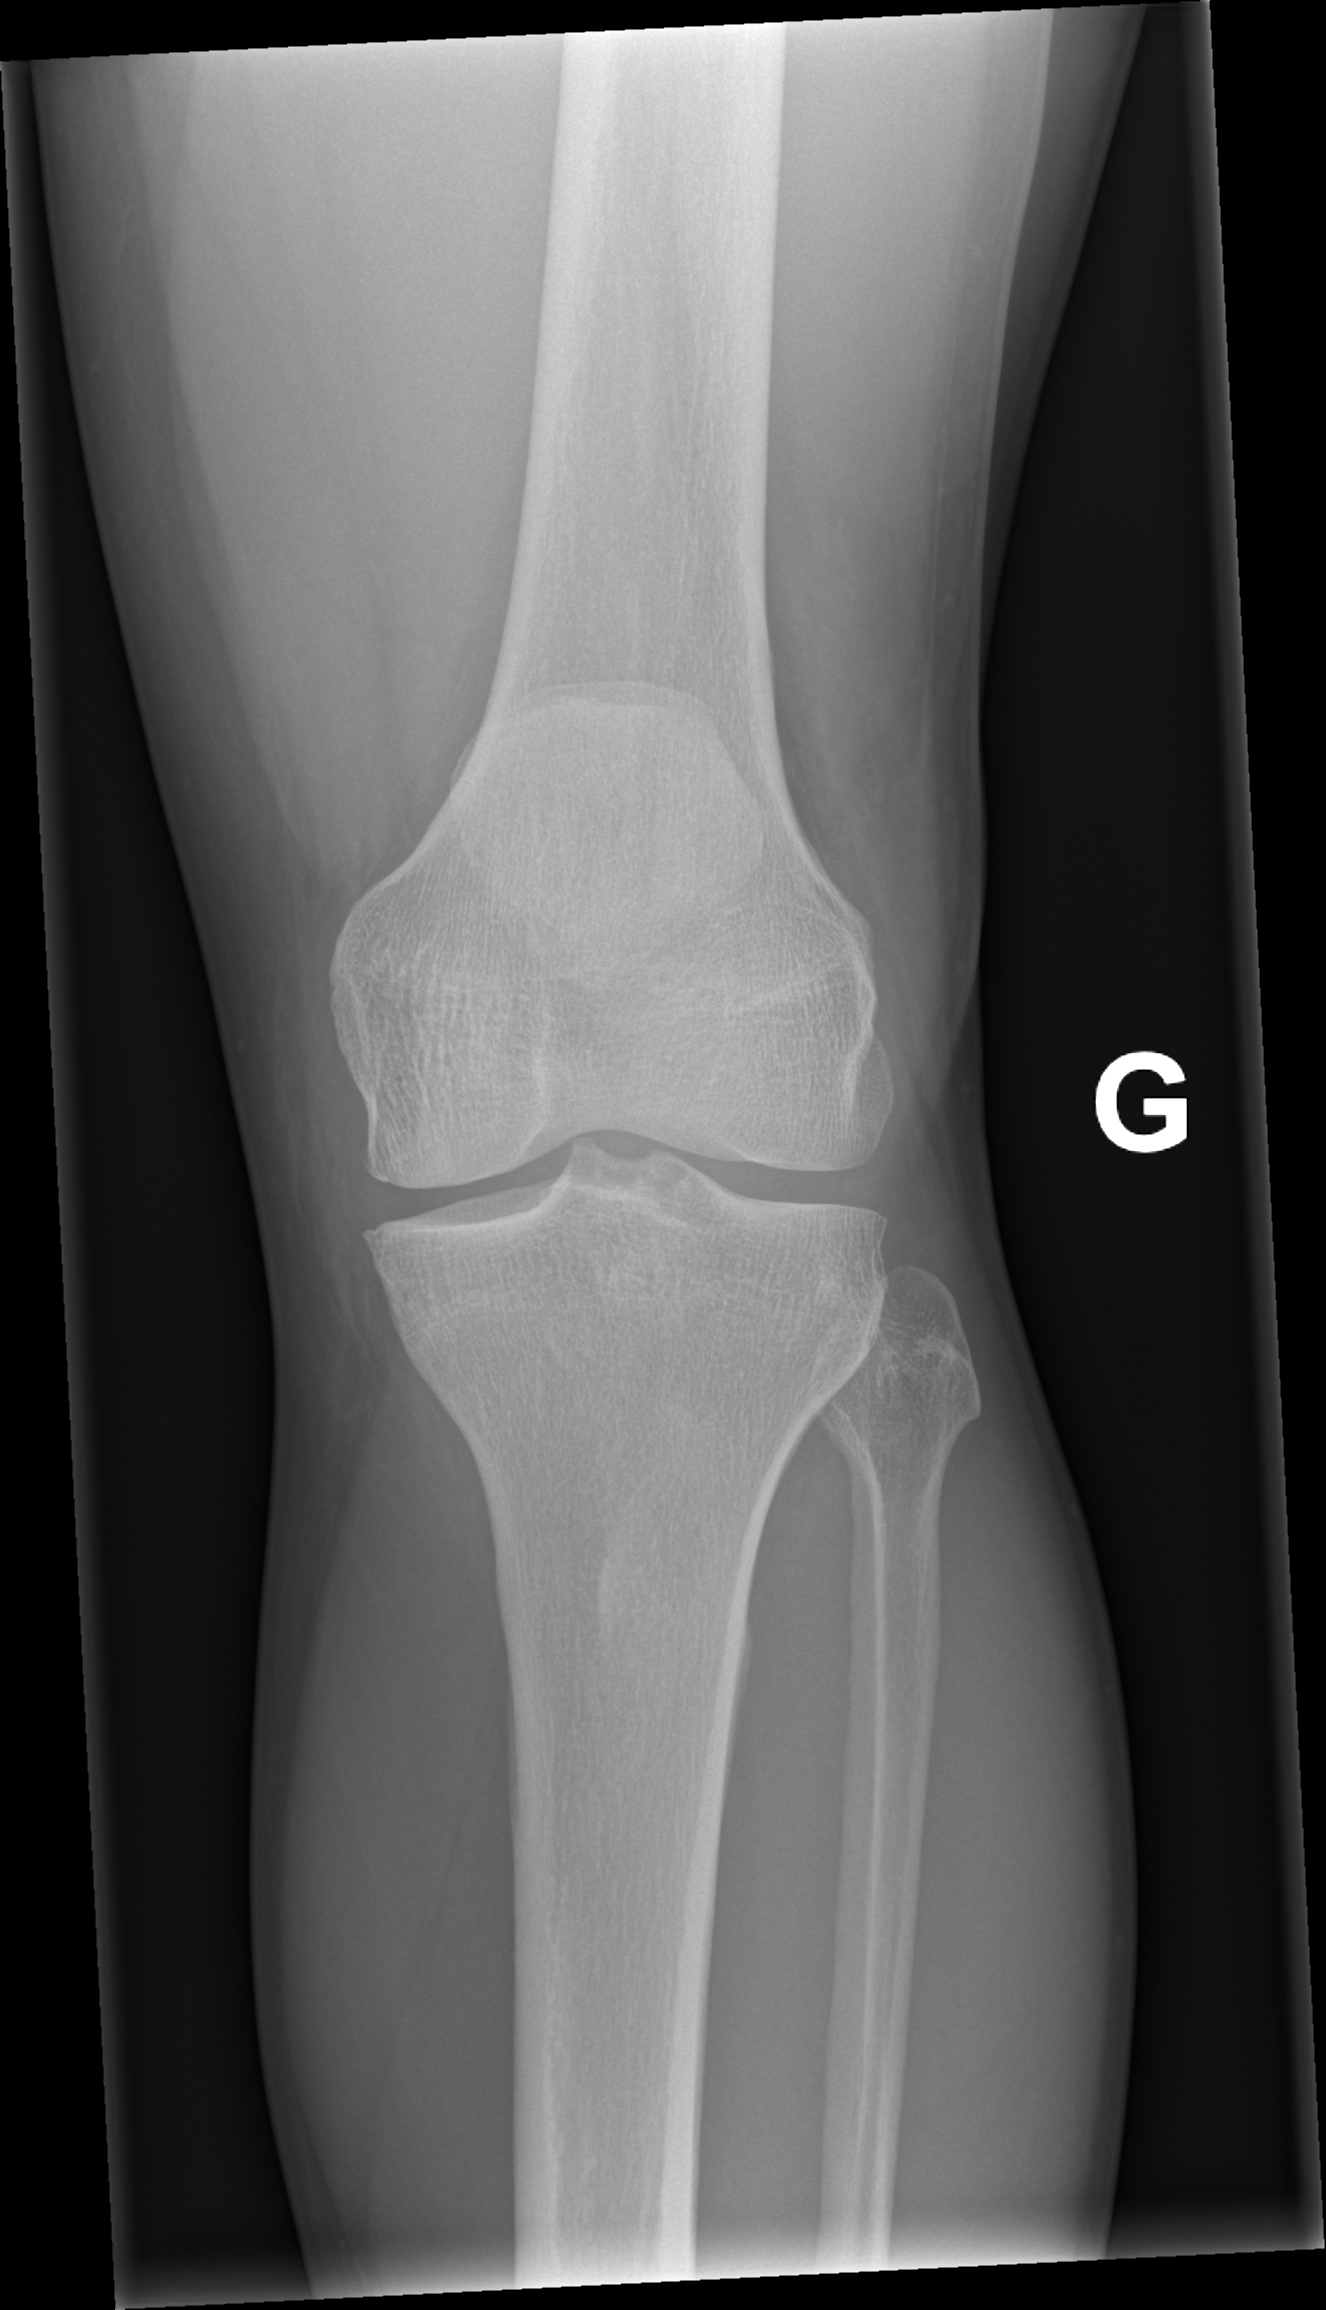

A l’examen clinique, le genou est légèrement tuméfié. La rotule semble ascensionnée et un creux est palpé sur le trajet du tendon rotulien. L’extension active est impossible. Sur les radiographies standards face et profil du genou, la rotule est ascensionnée.

Lorsque l’incidence axiale (ou défilé fémoro-patellaire, genou fléchi à 30°) est réalisée, l’image est décrite comme un « lever de soleil » avec une disparition de l’interligne articulaire et la superposition de la rotule avec les condyles fémoraux.

L’ultrason ou l’IRM peut confirmer le diagnostic de lésion du tendon rotulien et de différencier une rupture partielle d’une rupture complète. Le traitement est chirurgical.